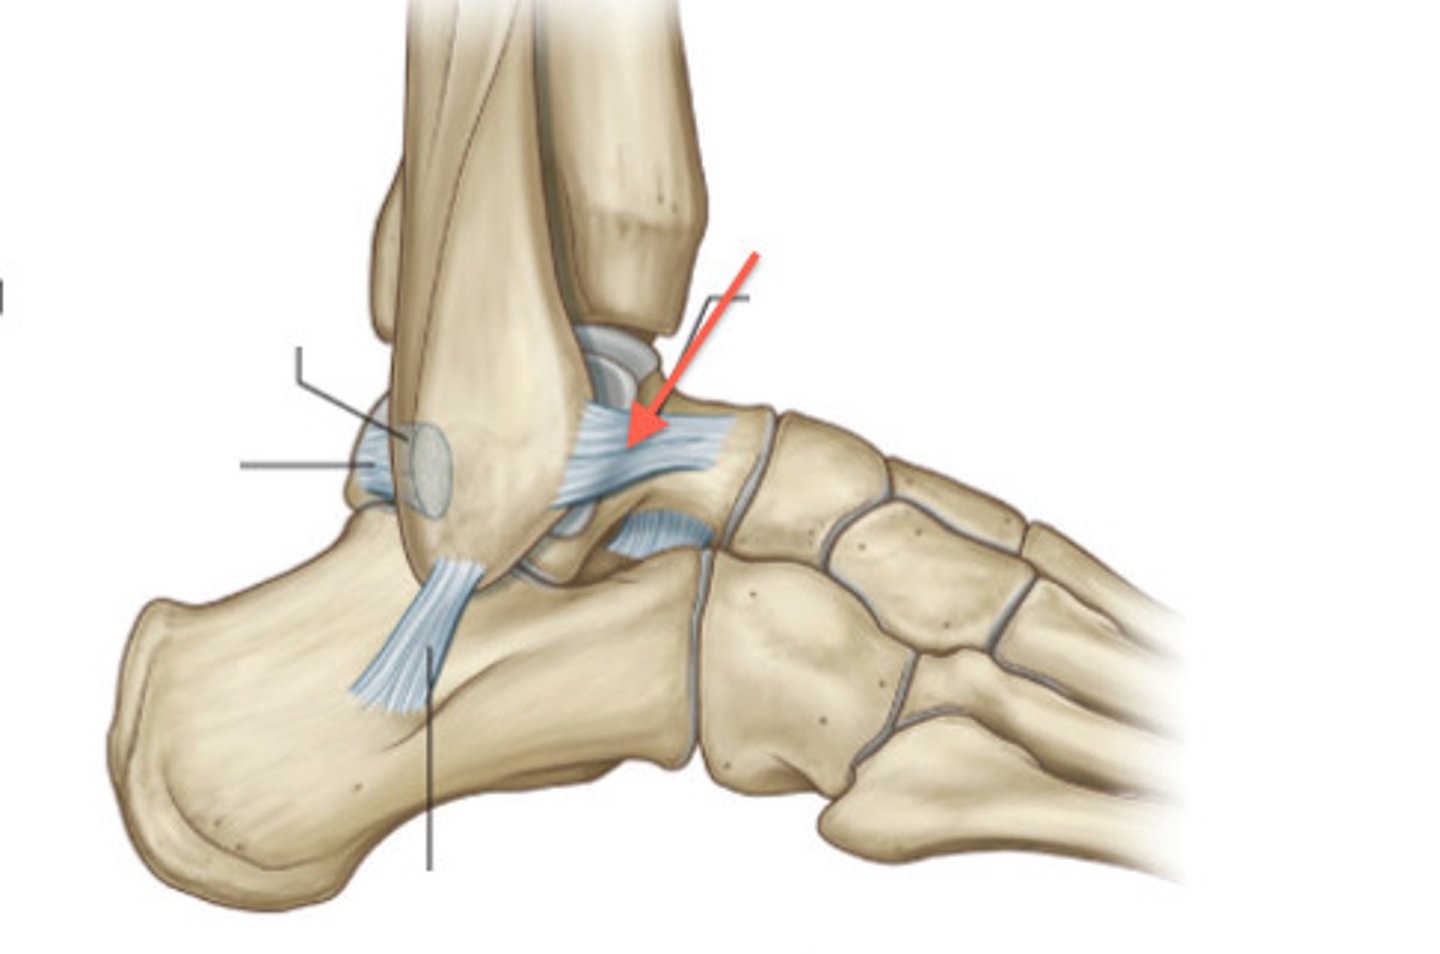

What ligament stabilizes the talus within the mortise joint?

Posterior talofibular ligament

What ligament limits inversion and dorsiflexion?

Calcaneofibular ligament

What ligament limits inversion and plantarflexion?

Anterior talofibular ligament

Most frequently injured ligament in ankle and foot complex

Most common injury mechanism for anterior talofibular ligament sprain

Inversion + plantarflexion during weight bearing

The relative inability of the _______ ________ to block the medial side of mortise joint contributes to anterior talofibular ligament sprains.

Medial malleolus